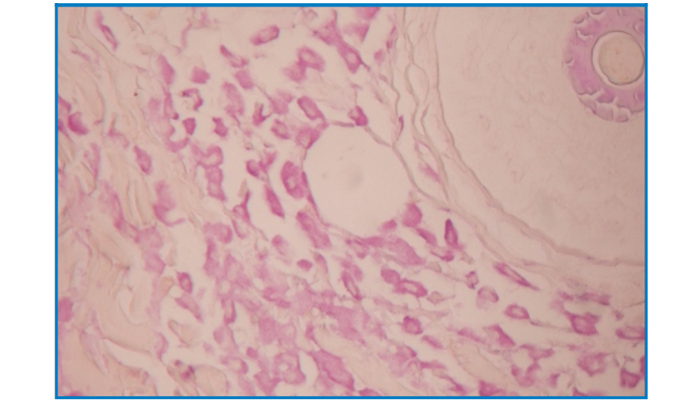

Mast Cell Stain

(Aldehyde fuchsin-OG6 staining method)

Intended for staining examination of histological mast cell.